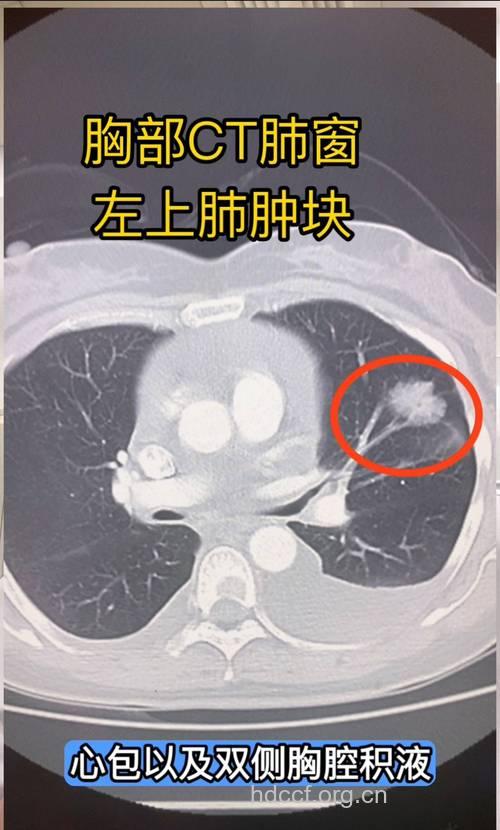

7、女性朋友们每年最少进行一次胸部X光拍片以了解肺部情况。另外目前国内最先进的技术是PET/CT检查具有简便、安全、准确、无创的特点,是一种排查肺部肿瘤的最佳手段。

以上为您介绍了女性肺肿瘤早期症状,女性预防肺肿瘤比较科学和稳妥的办法是常常定期到医院进行身体健康查体,以便于早发现、早治疗。半年到一年做胸透一次,这时即便发现了小的肺部肿瘤,尽早治疗做手术,成功率很高,不仅完全可以治愈,而且花钱不多。